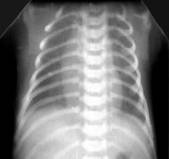

Умеренное снижение пневматизации легких, различимы воздушные бронхограммы, границы сердца чёткие (Рис.4).

Рисунок 4 Рентгенограмма грудной клетки в прямой проекции в горизонтальном положении. ( Диагностика и лечение РДС недоношенных // метод. Рекомендация, 2007)